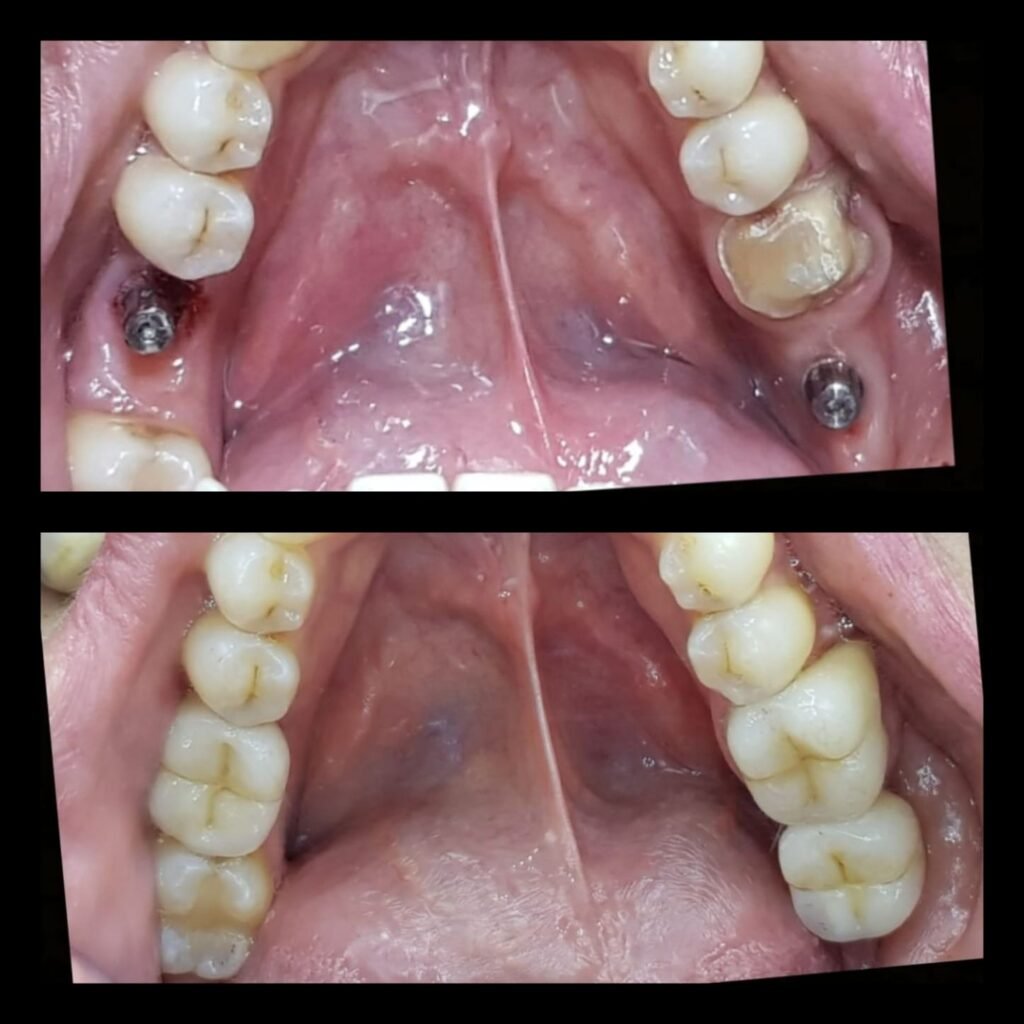

All on 4 total restoration

Avant et après

Avant et après pose d’implant dentaire à Agdal par dentiste spécialisé

Sourire amélioré après pose d’implant dentaire par dentiste à Agdal